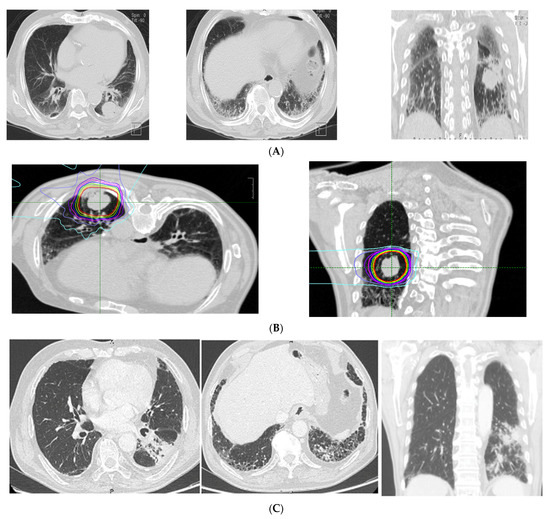

3.2. CT Findings Associated with ILD